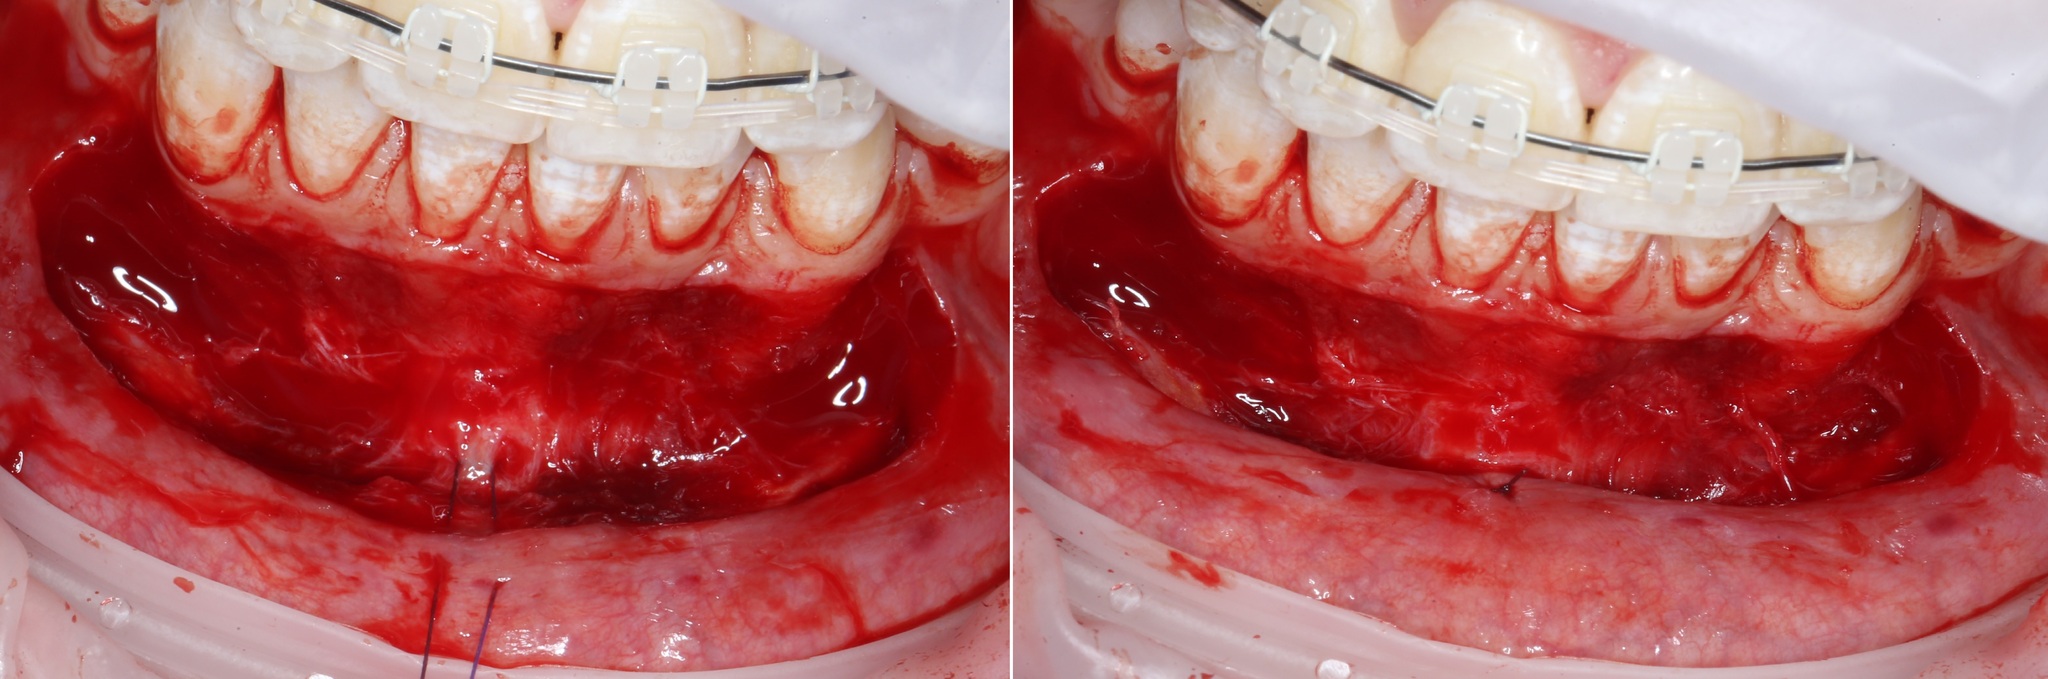

После проведенной анестезии границы слизистых видно отчетливее:

Там, где «вздулось», – подвижная слизистая оболочка, где нет – прикрепленная десна.

Разрез проводится как раз на их границе:

Разрез необходимо делать не до кости, а до надкостницы.